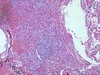

* granulation tissue

* skin

* wound healing

* early stage

* loose watery material in background (pinkish material) = ECM = fibrin, fibronectin, collagen

* lots of inflammatory cells

* many tiny, thin-walled blood vessels

* big blue "angry looking" cells = highly activated fibroblasts- producing lots of ECM and laying down collagen